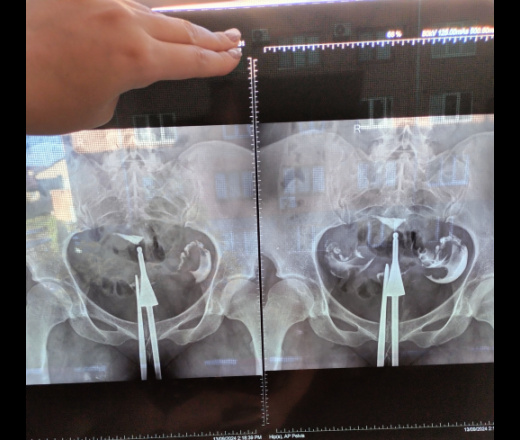

Врач сказал что маточных труб не проходимы, посмотрите пожалуйста

Извините, но вы сами разместили описание, в котором написано, что контраст в брюшной полости (я бы написал,  что в полости малого таза), поступить туда контраст может только через маточные трубы, значит трубы проходимы

Мой врач категорически настаивает на ЭКО, говорит что трубы не проходимы, ее не смущает заключение другого врача

По таким снимкам лично я написал бы, что есть признаки проходимости труб